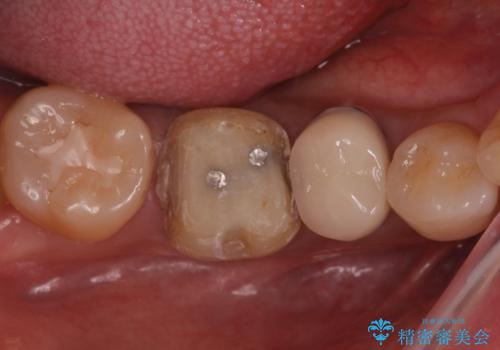

- 口を開けたときに下の歯の銀歯が目立つから白くしたいとのことで来院されました。

根管治療はご希望されなかったため、被せ物のみをやり替えていきます。